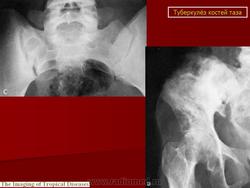

Артритическая фаза (при переходе процесса на сустав) на рентгенограммах характеризуется усилением остеопороза, который постепенно распространяется на все кости нижней конечности. Суставная щель асимметрично суживается, больше в верхне-наружных отделах. В дальнейшем сужение суставной щели достигает значительной степени. Суставные поверхности костей теряют свои очертания, их контуры становятся нечеткими, неровными. Выявляются краевые, без четких контуров содержащие секвестры, очаги деструкции костной ткани. Последние могут вызывать значительные разрушения вертлужной впадины, головки и даже шейки бедренной кости, смещение головки бедра вверх.

Стадия затихания характеризуется появлением четких контуров очагов деструкции в вертлужной впадине и в головке бедра, затем ободка склероза вокруг них. Остеопороз уменьшается. Появляются признаки репаративных процессов в виде толстых, расположенных вдоль силовых линий костных балок и уплотнение, склерозирование замыкательных пластинок. Могут выявиться в мягких тканях остаточные натечные абсцессы в виде более или менее плотных теней с признаками обызвествления. Остаточные каверны определяются в виде очагов деструкции костной ткани с достаточно четкими контурами и зоной реактивного склероза вокруг, с секвестрами в центре.